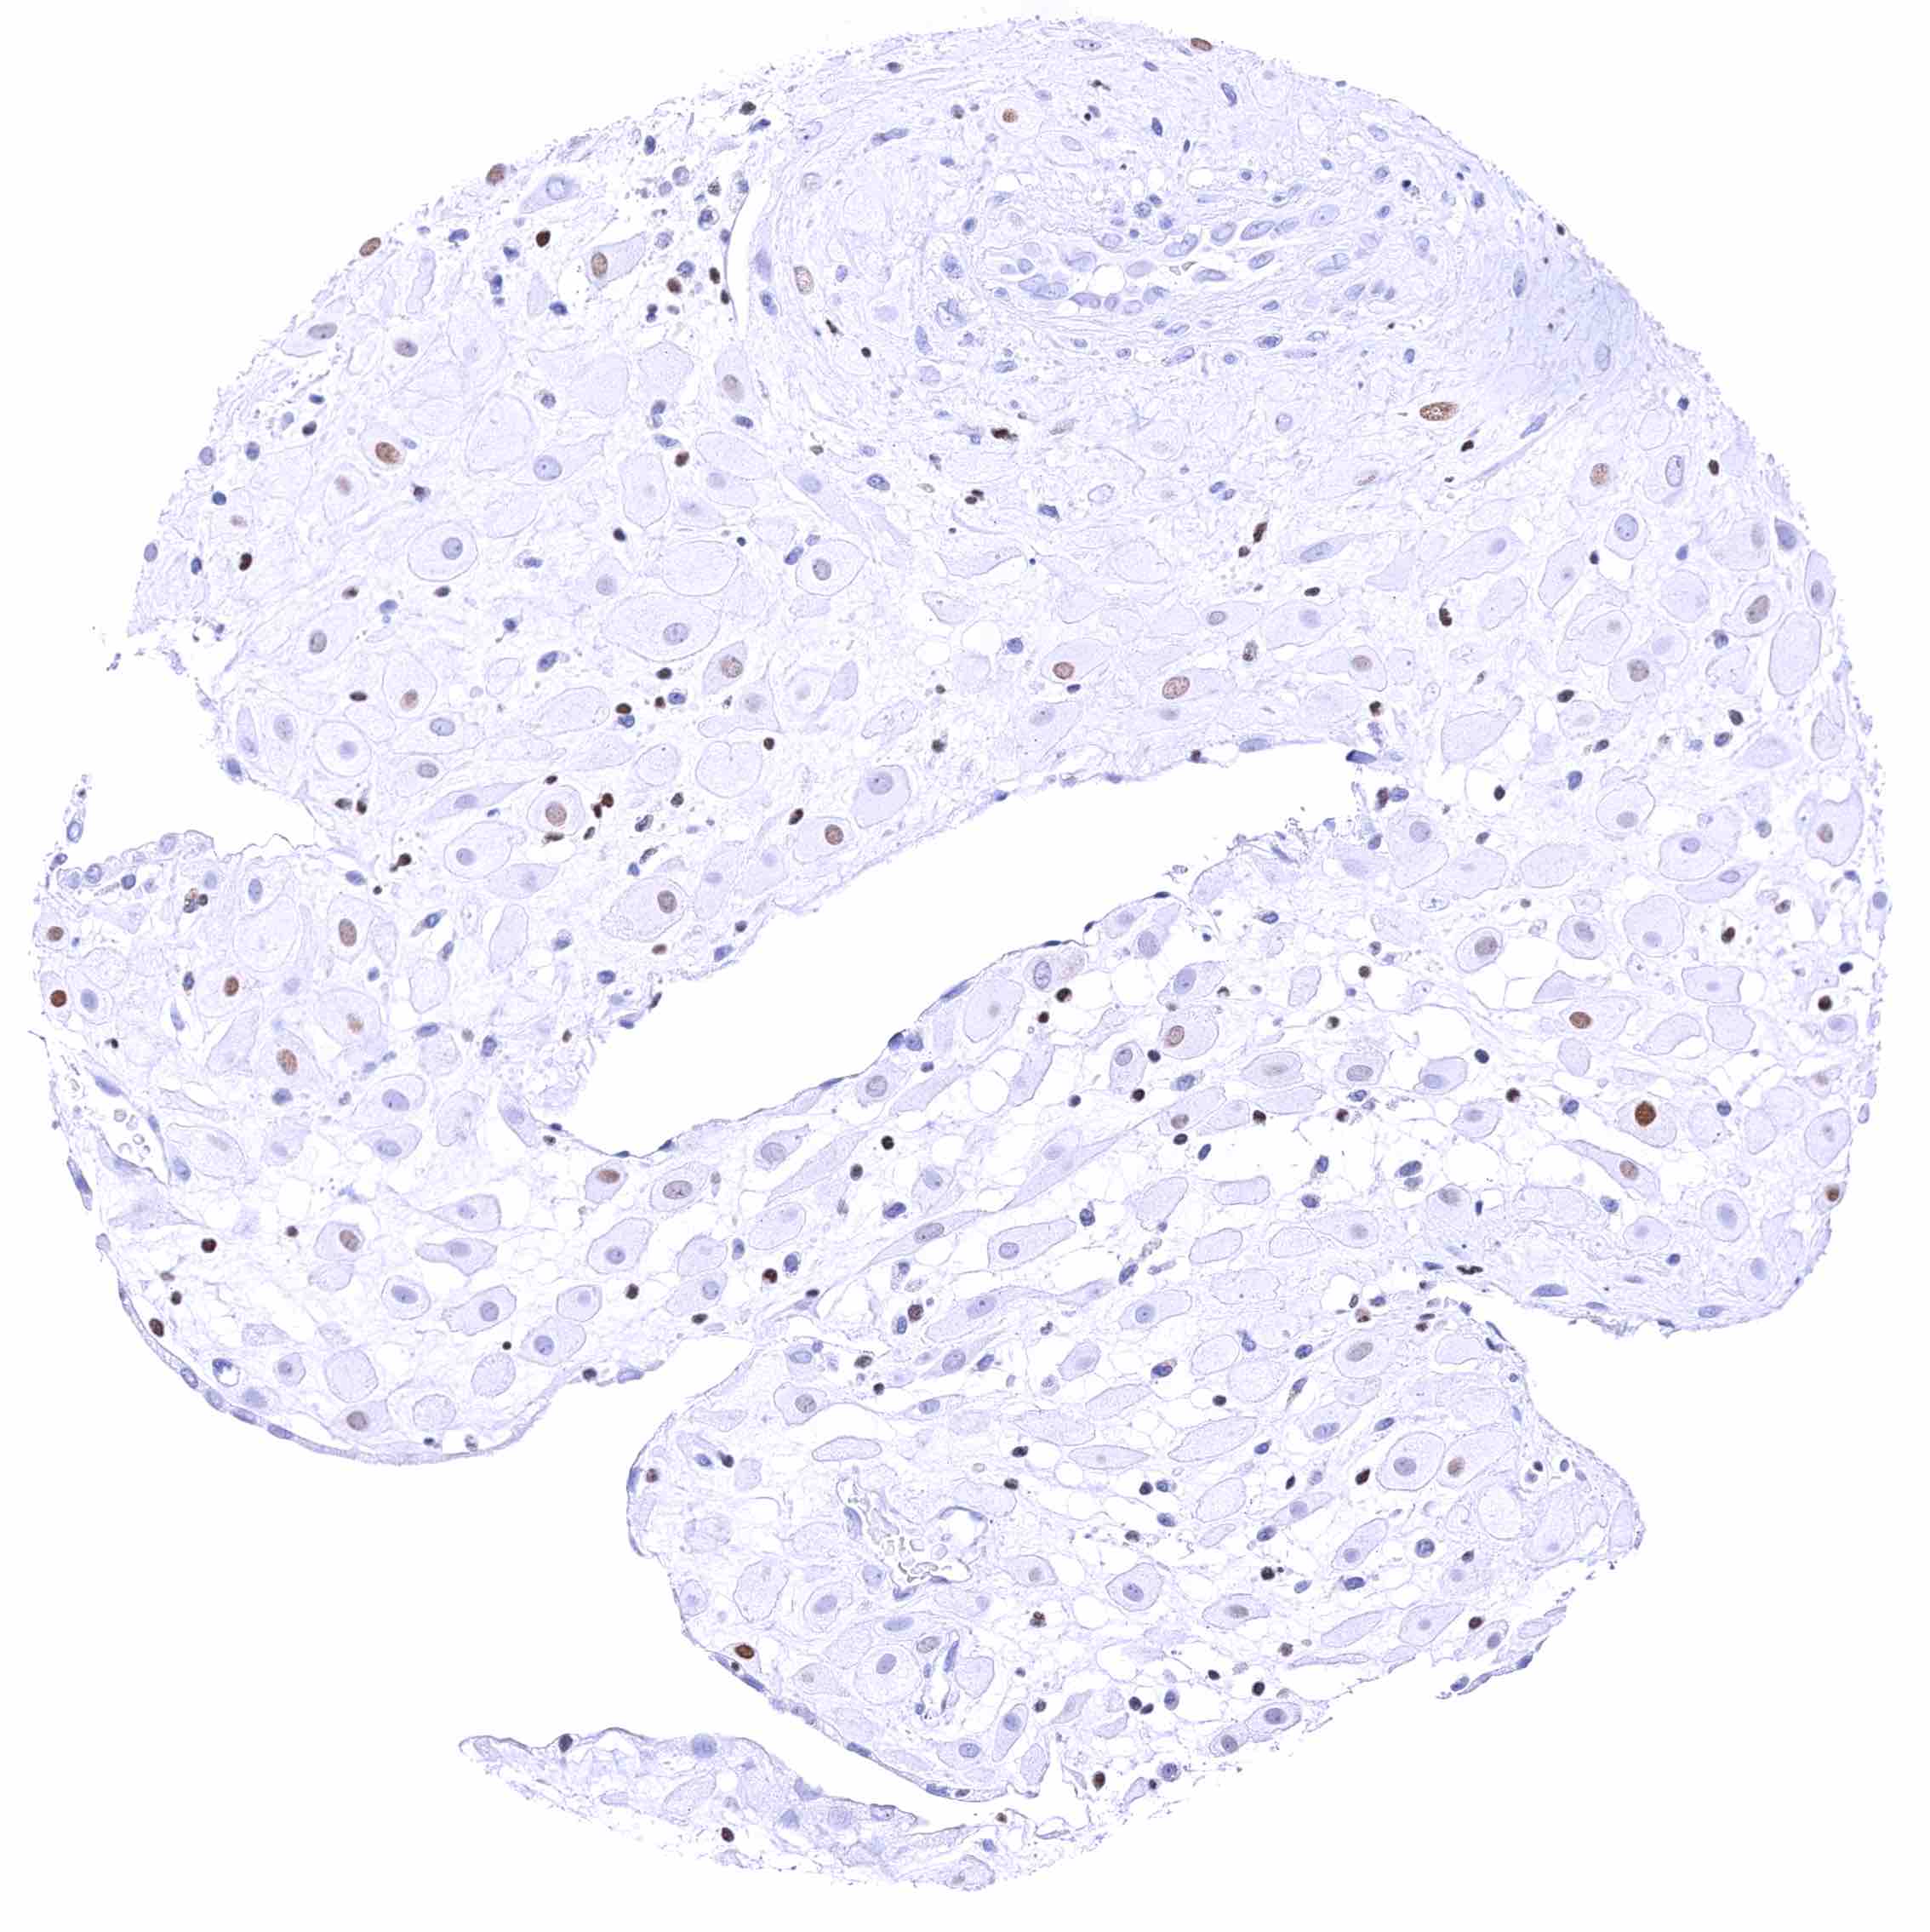

Epididymis (Caput) – Moderate to strong, nuclear GATA3 immunostaining of tall columnar cells nd of basal cells.